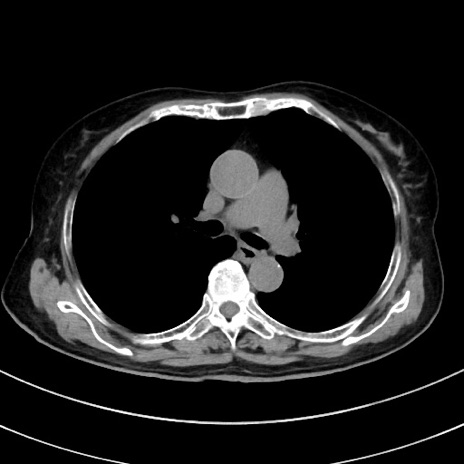

症例33(横断像)

【症例】70歳代 女性

【主訴】心窩部痛

【現病歴】延髄病変の精査・加療にて神経内科入院中。本日より心窩部痛あり。

【既往歴】虫垂炎

【身体所見】右下腹部を中心に圧痛と反跳痛あり。

【データ】WBC 10900、CRP 0.02